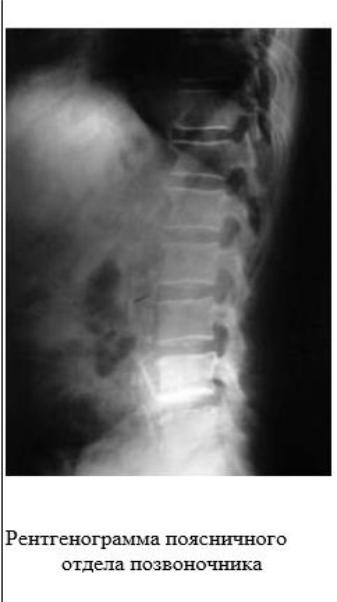

Больной М. 65 лет обратился в поликлинику с жалобами на одышку при небольшой физической нагрузке, периодически малопродуктивный кашель (особенно при переохлаждении, в сырую погоду), ощущение хрипов и тяжести в груди, сердцебиение.

Из анамнеза: курит 30 лет по пачке в день. Одышка появилась 3 года назад и стала прогрессировать за последний год. В течение последнего месяца, после перенесѐнного ОРЗ, одышка усилилась, мокроты стало выделяться больше, она приобрела жѐлто-зелѐный цвет. Несколько лет наблюдается с диагнозом «стенокардия II ФК», 2 года назад перенѐс крупноочаговый инфаркт миокарда переднебоковой, в связи с чем постоянно принимает Соталол, Кардиомагнил, Моночинкве (изосорбида-5-мононитрат).

Объективно: общее состояние средней тяжести. Лѐгкий акроцианоз. Больной пониженного питания, грудная клетка расширена в поперечнике, при перкуссии грудной клетки - лѐгочный звук с коробочным оттенком. При аускультации лѐгких - дыхание ослабленное, в нижних отделах лѐгких сухие низкотембровые и пневмосклеротические хрипы, выдох удлинѐн.

При осмотре ЧДД - 24 в минуту, ЧСС - 100 в минуту. АД - 130/80 мм рт. ст.

На ЭКГ: рубцовые изменения на боковой стенке левого желудочка. Единичные желудочковые экстрасистолы.

Спирография: ЖЕЛ - 52%, ОФВ1 - 37%, Тест Тифно - 57,2.

На рентгенограмме органов грудной клетки - признаки эмфиземы и пневмосклероза лѐгких.

Общий анализ мокроты: лейкоциты – до закрытия полей зрения, нейтрофилы - 90%, лимфоциты - 10%.